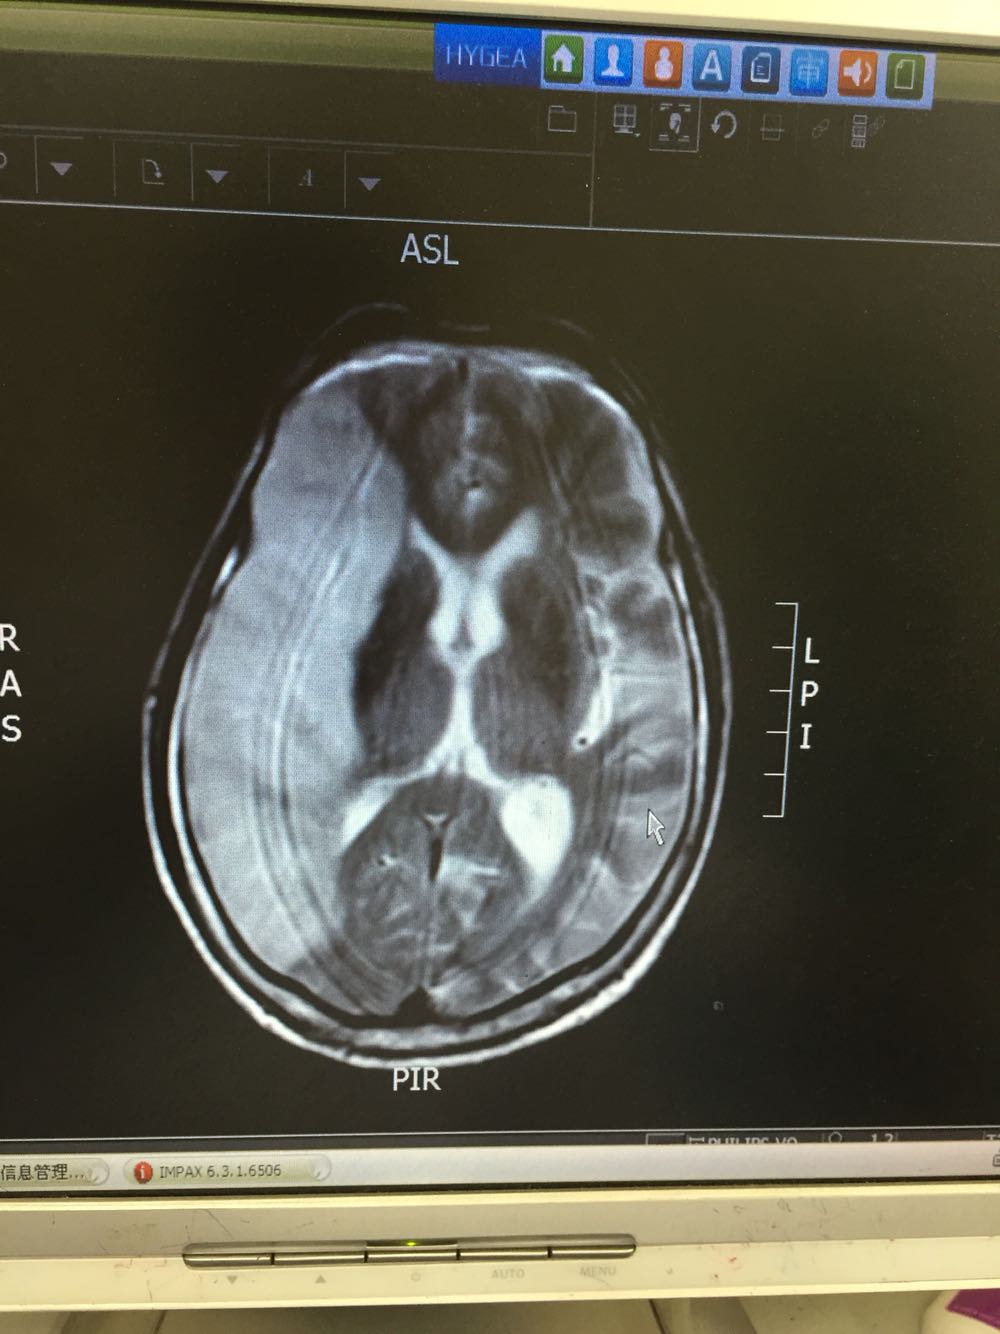

72岁男患,主因左侧肢体无力言语不能3日入院,既往否认高血压、糖尿病史 该患者于入院前三日无明显诱因出现左侧肢体无力伴言语不能,无头晕、恶心呕吐,无抽搐发作,伴有排尿障碍,于当地治疗3日无好转,为求进一步诊治来我院

血压145/92 神清,言语不能,双瞳等大同圆,伸舌居中,左侧肢体肌力0级,右侧肢体肌力4级 双下肢病理症未引出 颈强阴性

患者急性右侧大脑中动脉闭塞导致大面积脑梗死。遗留左侧肢体瘫痪可能性大。目前一般状态尚可